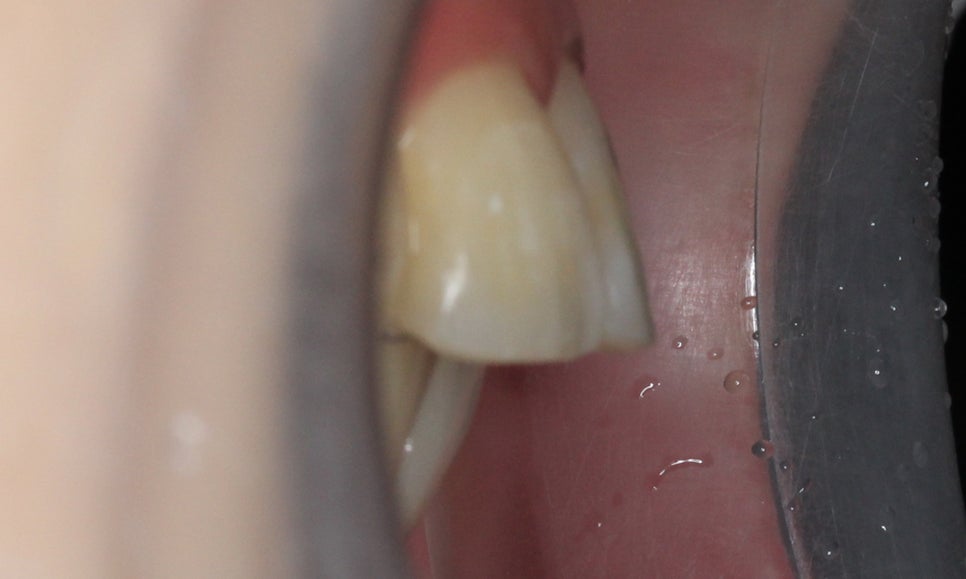

전치부의 돌출감을 아래에서 살펴보면

상악의 입툭튀 정도를 가늠할 수 있는데요,

대치동치과에서는 이러한 돌출입 Case를

효과적으로 교정하기 위해

다양한 치아교정 방법과

브라켓을 적용하고 있습니다.

이어서 Overjet사진을 보시면

상악과 하악의 돌출감 차이를

확인할 수 있는데요,

상악의 성장이 과도할 경우

위처럼 윗니가 과도하게

전방으로 튀어나오는 증상이 나타나거나

혹은 턱의 길이가 짧고 무턱증상을 보일 수 있습니다.